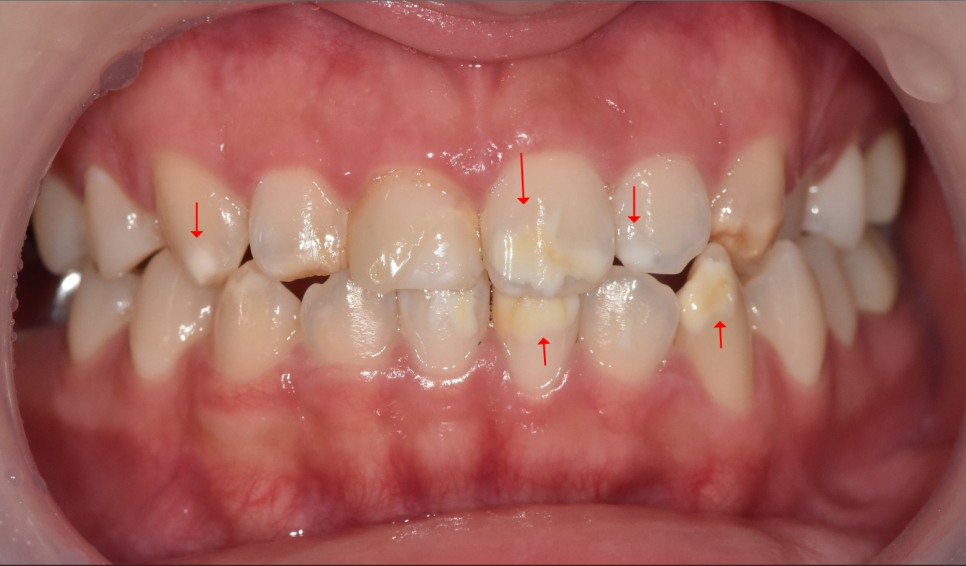

특히 왼쪽 송곳니는 탈회가 진행돼서 초기 충치로 변하고 있는 상태였어요.

충치가 진행된 모습

게다가 치아 길이도 전체적으로 가지런하지 않았습니다.

아래 앞니도 하얀 반점이 여러 군데 있긴 했지만,

특히 왼쪽 아래 송곳니의 반점이 가장 도드라져 보입니다.

그래서 처음엔 위 6개 치아와 왼쪽 송곳니 1개

총 7개의 치아를 라미네이트로 진행할까 했지만,

문제가 있었습니다.